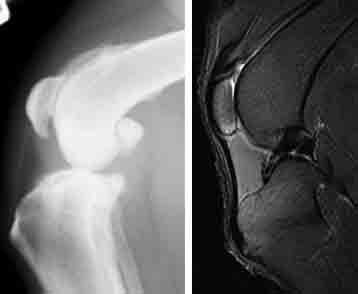

Depending on the research question to be answered several different imaging modalities can be used in musculoskeletal imaging. Magnetic Resonance Imaging provides images of the greatest range of tissues including bone marrow and changes in the internal structure of a joint, including articular cartilage changes, whereas CT can provide detailed images of bone structure.

Our range of magnets available allows MR imaging of beagles at up to 9.4T. Plain radiographs can illustrate basic morphometric changes with either contrast radiography or ultrasound adding details of the internal structure of joints. Nuclear medicine studies provide quantitative information on bone metabolic turnover and studies can be focused on a specific area or can include the entire skeletal system.

From left to right: Radiograph of a dog knee with osteoarthritis; MR image of a normal dog knee.